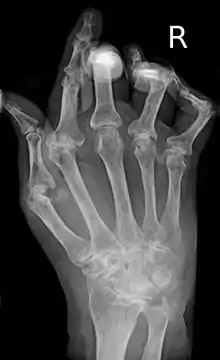

| A hand severely affected by rheumatoid arthritis. This degree of swelling and deformation does not typically occur with current treatment. | |